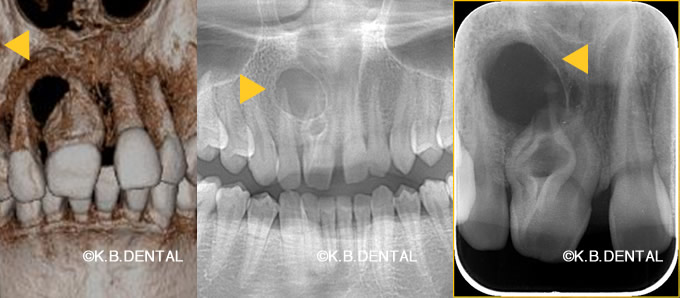

正中過剰埋伏歯(せいちゅうかじょうまいふくし)

正中過剰埋伏歯 症例

正中過剰埋伏歯の症例です。鼻腔底直下にあるので、静脈内鎮静を使い無痛抜歯で対応しました。抜歯が怖い方はご相談下さい。

料金は保険適用で約10,000円の治療費用です。